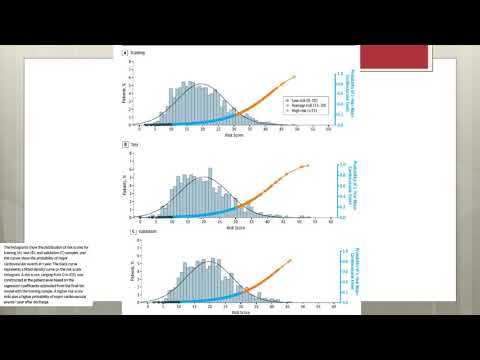

Predictores a corto termino de enfermedad cardiovascular en adultos mayores. Dr. Gerardo Albarracín. Residencia de Cardiología. Hospital C. Argerich. Buenos Aires